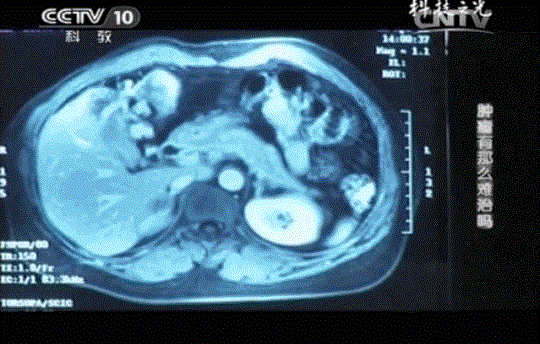

王女士的肝臟上出現(xiàn)了一個(gè)直徑約為8cm的肝轉(zhuǎn)移腫瘤。毫無征兆就出現(xiàn)的肝轉(zhuǎn)移腫瘤讓王女士徹底地絕望了。她立即決定放棄治療,與家人一起走完人生最后的半年時(shí)間。

不僅如此,連續(xù)4個(gè)月的CT結(jié)果對(duì)比分析,肝轉(zhuǎn)移瘤從8公分縮小到2.5公分,腫瘤標(biāo)記物指標(biāo)回歸正常,這些都說明腫瘤正在被免疫細(xì)胞一點(diǎn)點(diǎn)消滅。